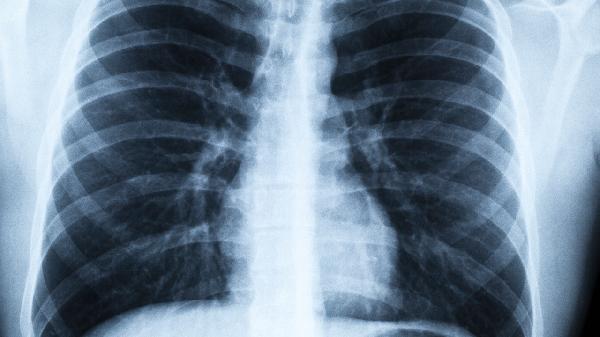

肺癌有哪些偽裝

肺癌的常見癥狀主要是頑固的咳嗽與血痰,但切莫忘記這是一種喜歡玩點小花招的惡性腫瘤,常借助于面具來混淆視線,逃避醫(yī)學的打擊。肺癌有哪些偽裝據(jù)癌癥專家觀察,乳頭病變僅是其常用的面具之一,還有5張面具值得人們警覺:

肺癌臨床表現(xiàn)是多樣性的,特別是有吸煙史的中老年人,應(yīng)常規(guī)攝X線胸片,必要時進行肺部CT掃描,以便早期發(fā)現(xiàn)可能存在的癌病灶,盡量減少肺癌的漏診。